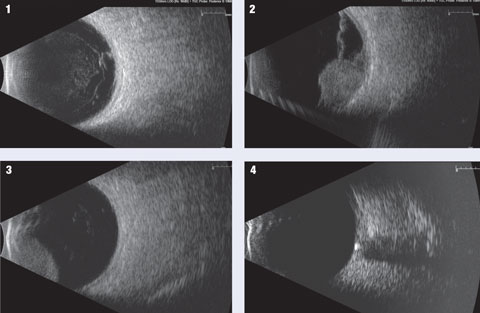

Breast Tomosynthesis

One in four cancer deaths among American women are caused by breast cancer, the second most common type of cancer affecting women. As high as that statistic may be, however, it’s 20 percent lower than it was a decade ago, thanks to improved screening techniques for breast cancers.

Tomosynthesis can best be described as 3-D mammography. The Federal Food and Drug Administration approved the technique in 2011. A specialized imaging machine is used to take dozens of x-ray scans of breast tissue from multiple angles. The images are then compiled by a computer into a three dimensional portrait of the inside of the breast.

The earlier breast cancer is detected, the more responsive it is to treatment. Three-dimensional breast cancer screening increases the likelihood of detecting small cells in the earliest disease stages that may be obscured by denser surrounding tissue.

Breast tomosynthesis also reduces the need for additional testing. Right now, one in ten routine mammograms yields inconclusive results, necessitating a repeat mammogram. This frightens many women unnecessarily.

Many cancer specialists fully expect breast tomosynthesis to replace conventional mammography within the next decade.